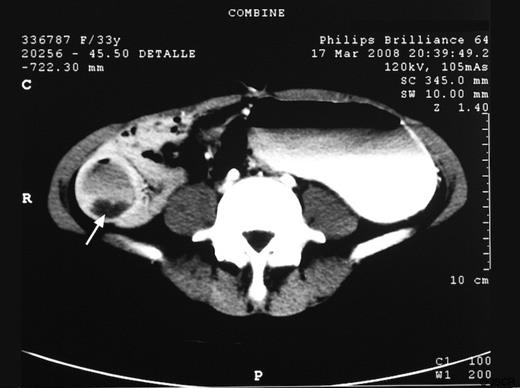

The cholangio-MRI and the abdominal CT scan also showed the diverticulum (figure 3), as well as signs of upper intestional malrotation, absence of the pancreatic tail, polysplenia and an hepatic artery that emerged from the superior mesenteric artery.

CT appearance of the intraluminal duodenal diverticulum (arrow).